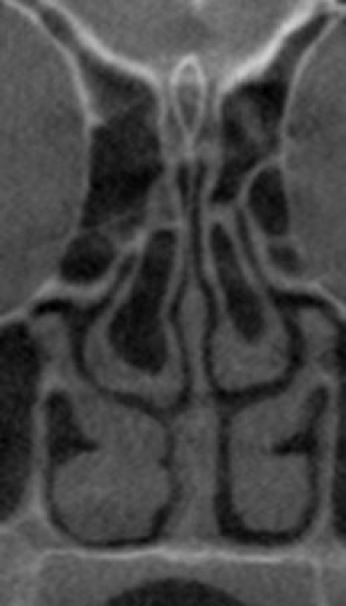

Background: Pneumatization of turbinates, also known as concha bullosa (CB), is associated with nasal septal deviation and sinonasal pathologies. This study aims to evaluate the performance of deep learning models in detecting CB in coronal cone-beam computed tomography (CBCT) images.

Methods: Standardized coronal images were obtained from 203 CBCT scans (83 with CB and 119 without CB) from the radiology archives of a dental teaching hospital. These scans underwent preprocessing through a hybridized contrast enhancement (CE) method using discrete wavelet transform (DWT). Of the 203 CBCT images, 162 were randomly assigned to the training set and 41 to the testing set. Initially, the images were enhanced using a CE technique before being input into pre-trained deep learning models, namely ResNet50, ResNet101, and MobileNet. The features extracted by each model were then flattened and input into a random forest (RF) classifier. In the subsequent phase, the CE technique was refined by incorporating DWT.